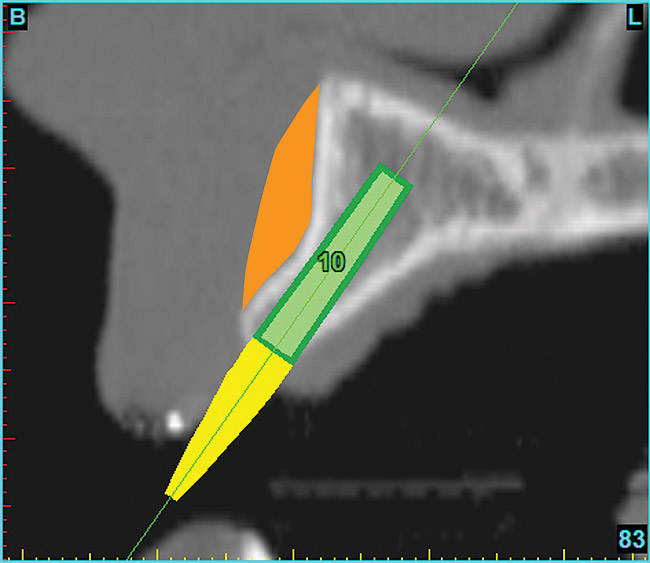

Using the interactive treatment-planning software application, the scan data was assimilated and both potential lateral incisor implant receptor sites were evaluated. It is a combination of the data and the methodology used to interpret the data that is the basis for defining a new paradigm in diagnosis and treatment planning. Proper evaluation of these images and correct use of the interactive treatment planning software tools is essential in creating a decision tree of treatment options. First, the data from the scan was reformatted into panoramic, axial, and cross-sectional images. The undistorted cross-sectional images revealed the residual alveolar bone in the area of the right lateral incisor. Then, a simulated schematic implant was placed within the bone with an abutment extension to help visualize the connection to the restorative position of the tooth (Figure 6). The Triangle of Bone® (TOB), a concept developed by the author to analyze bone quality, quantity, and disposition at prospective dental implant sites using CBCT scans, aided in determining available bone volume by defining a “zone” for proper implant placement18,19 (Figure 7).

After reviewing the CT data and the decision tree, the bone within the “zone” of the TOB was evaluated and found to be satisfactory for implant placement. Because the goal of implant dentistry is not the implant but the tooth that is placed, true restorative-driven implant dentistry must begin with the assumption that the implant position should remain consistent with the tooth it is replacing, and the final implant-supported restoration.12,22-26 The TOB aids the clinician in understanding the link between the implant position and the desired restorative goal. The base of the geometric shaped “zone” is visualized by starting at the widest area of alveolar bone facially and superiorly. The apex of the triangle is positioned to bisect the alveolar crest (Figure 7). The TOB, the overlay in the cross-sectional image, reveals whether adequate bone is available for implant placement. It also helps to identify concave facial bone defects, and accurately determine the width of bone at the crest. The author recommends using an interactive software application that provides the necessary measurement tools to accurately assess the bone anatomy.

Figure 7  SOFTWARE IMAGING The determination of the "zone" for proper placement.

Figure 7